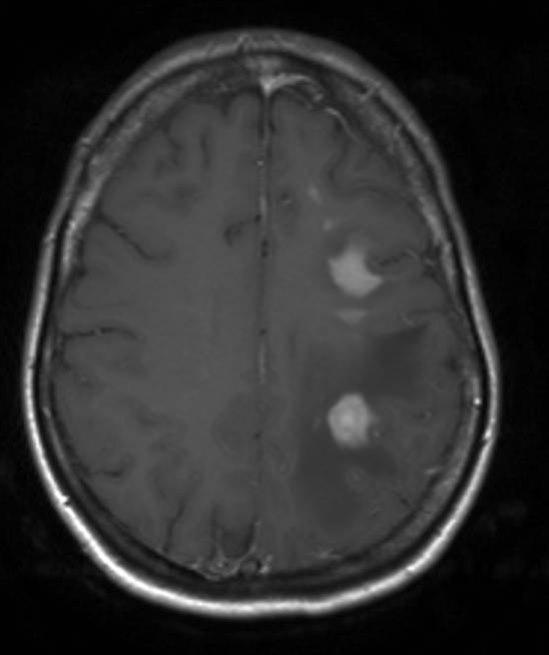

Primært CNS lymfom, aksialt snitt

Gjengitt med tillatelse av Radiologisk avdeling, Universitetssykehuset Nord-Norge